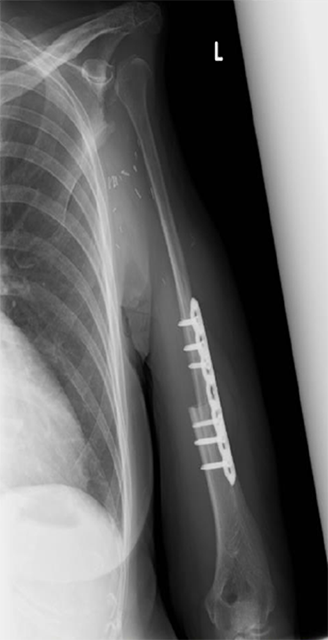

(3)腓骨移植

下腿にある腓骨と呼ばれる長管骨を採取し、移植します。骨と同時に皮膚も移植することができるため、骨欠損と軟部組織欠損を同時に治療することが可能です。また、血流のある骨移植であるため感染に対しても強く、感染性偽関節症例にも適応されます。

上腕骨腫瘍に対し、広範切除術と腓骨移植術を行った。